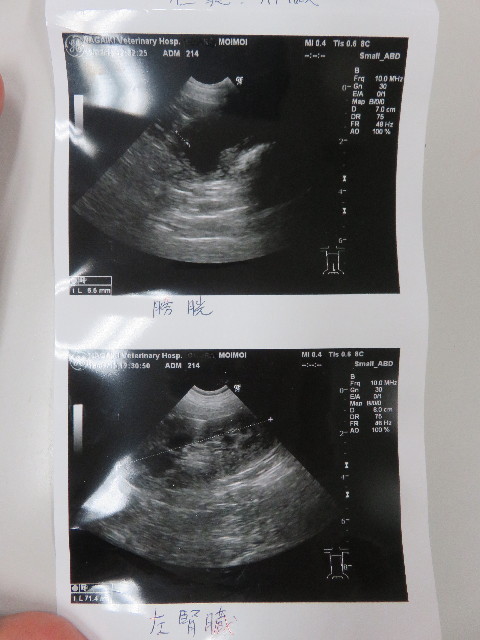

それってどうなの?肝臓さんは大丈夫なの?と思い先生にちょっときいてみました。

●肝臓への負担は、血液検査をマメにしていていつも問題がないのでそんなに心配しなくて大丈夫と思う。とのこと。